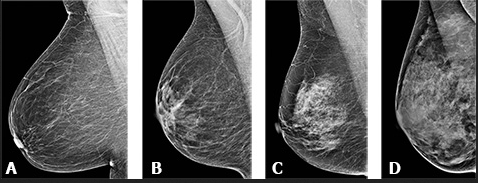

Acr тип плотности в

Acr тип плотности в 112 фото